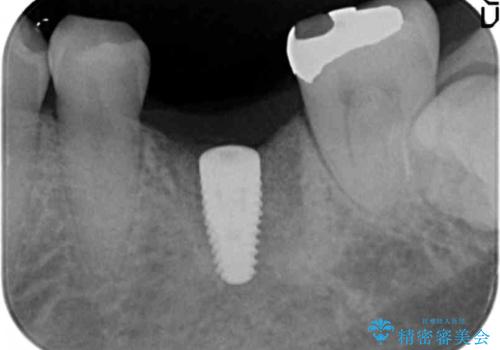

強い噛み合わせによる歯牙破折後のインプラント治療

- 強く噛みしめる癖や歯ぎしりにより歯が割れてしまい、抜歯後のインプラント治療を求めて来院されました。

ブリッジや入れ歯といった周囲の歯の負担を増やす方法ではなく、より強大な咬合力にしっかりと耐え噛むことのできるインプラントを用いた機能回復を計画します。

今回の治療では、周囲の歯に負担を増やし破折リスクを高めるブリッジや入れ歯ではなくインプラント治療を選択しました。